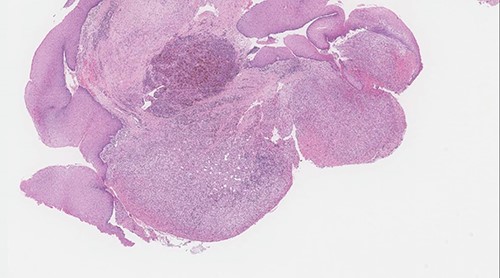

The post-operative course was uneventful, and the patient was discharged the same day with analgesics and anti-reflux medications. The patient was given appointment for follow in otolaryngology clinic one week after discharge for pathology review and reassessment. Pathology report revealed lobular capillary hemangioma with no evidence of malignancy. Histologic sections showed polypoidal squamous mucosa with associated superficial ulceration and fibrinoid necrosis (Figs 7 and 8). Submucosally, there was proliferation of small blood vessels arranged as lobules with surrounding granulation tissue and chronic inflammatory cells (Fig. 9). The endothelial cells were bland, spindled and lack dysplastic features. No atypical mitotic figures were identified. The squamous epithelium adjacent to the ulceration showed hyperplastic changes. After 2 months patient was re-evaluated again and reported improvement of his symptoms. Examination showed normal larynx with no signs of recurrence.

Polypoid squamous mucosa with ulceration and peripheral hyperplastic changes (original magnification: X40, H&E stain).

Surface ulceration with prominent fibrinoid necrosis (original magnification: X40, H&E stain).

Vascular proliferation arranged as lobules with adjacent chronic inflammation (original magnification: X200, H&E stain).